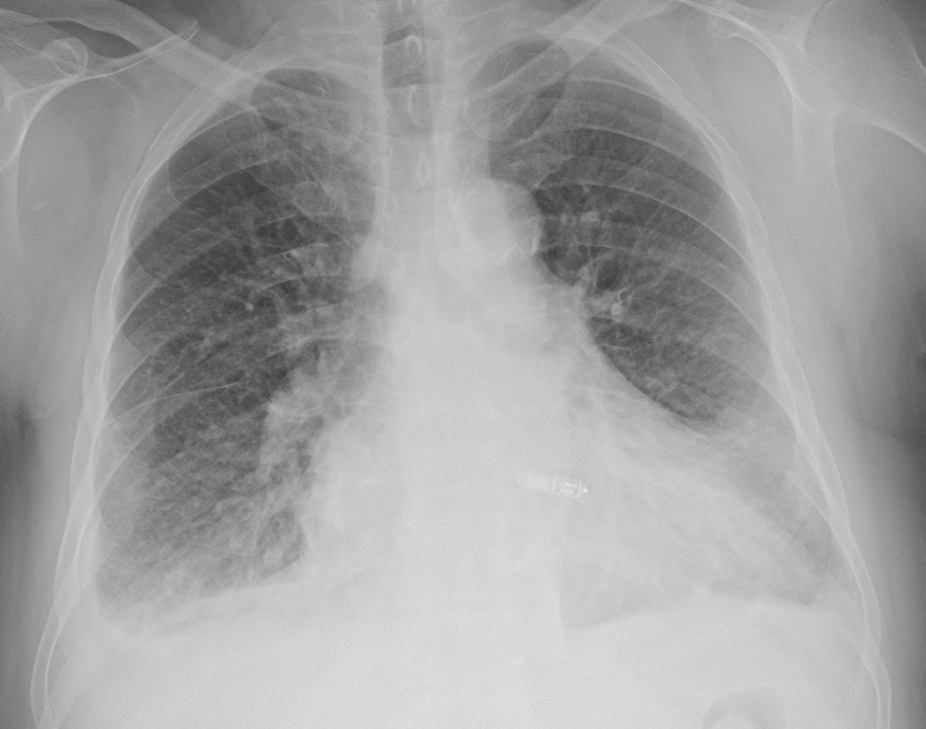

이식형 심장 사건 기록기 (Implantable loop recorder)

이식형 심장 사건 기록기 (ILR) 은 USB 메모리 스틱과 비슷한 납작한 모양의 작은 물체입니다. single-lead 심전도를 기록, 저장할 수 있는 기능을 가지고 있습니다. (최대 3년) 특정 서맥, 빈맥 부정맥이 발생할 경우 자동으로 심전도를 저장할 수 있습니다. 환자가 증상이 있을 때 추가적으로 심전도를 기록할 수 있습니다.

가장 작은 ILR 인 Reveal LINQ 는 4.48 cm x 0.72 cm 크기입니다.